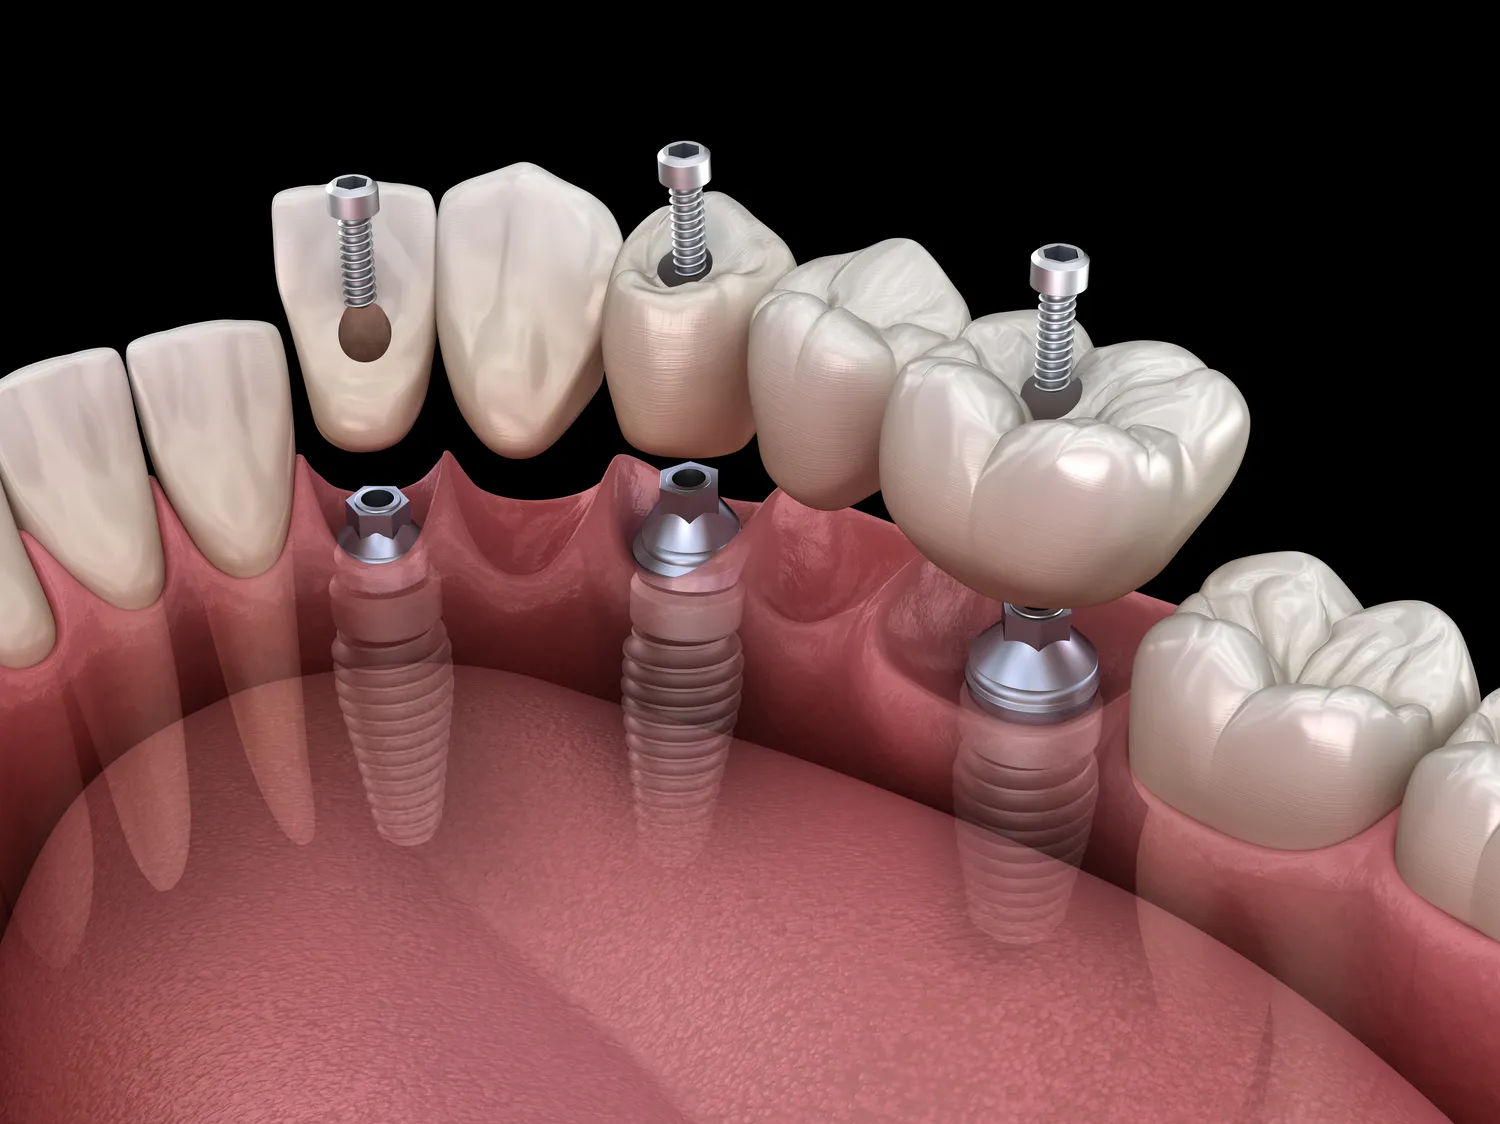

Choć leczenie nakładkami ortodontycznymi jest coraz bardziej popularną metodą korekcji wad zgryzu, istnieją także inne opcje terapeutyczne dostępne dla pacjentów pragnących poprawić swój uśmiech. Jedną z najczęściej stosowanych alternatyw są tradycyjne aparaty stałe, które składają się z metalowych zamków i drutów mocujących. Ta metoda jest szczególnie skuteczna w przypadku bardziej skomplikowanych wad zgryzu i może być stosowana u pacjentów w każdym wieku. Inną opcją są aparaty ruchome, które mogą być stosowane głównie u dzieci i młodzieży w celu korygowania niewielkich wad zgryzu lub jako przygotowanie do dalszego leczenia ortodontycznego. Dla osób dorosłych dostępne są także lingwalne aparaty ortodontyczne umieszczane po wewnętrznej stronie zębów, co sprawia, że są one praktycznie niewidoczne dla innych ludzi. W ostatnich latach pojawiły się także innowacyjne metody takie jak terapia miniimplantami czy zastosowanie technologii 3D do projektowania indywidualnych aparatów stałych lub ruchomych.